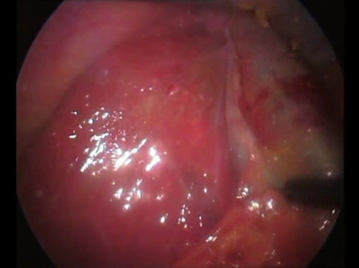

Une cœlioscopie réalisée a montré de multiples granulations blanchâtres disséminées dans la totalité du foie, le reste de l’exploration était sans particularité (Figures 6 ,7). Une cholé-cystectomie associée à une biopsie hépatique objectivant une granulation blanchâtre, ont été réalisées.

L’examen histologique de la pièce opératoire est celui d’une cholécystite chronique en poussée aiguë post-lithiasique, alors que la biopsie hépatique montrait un parenchyme hépatique siège d’une surcharge stéatosique modérée avec la présence de 3 follicules épithélio-giganto-cellulaires sans nécrose caséeuse (Figure 8).